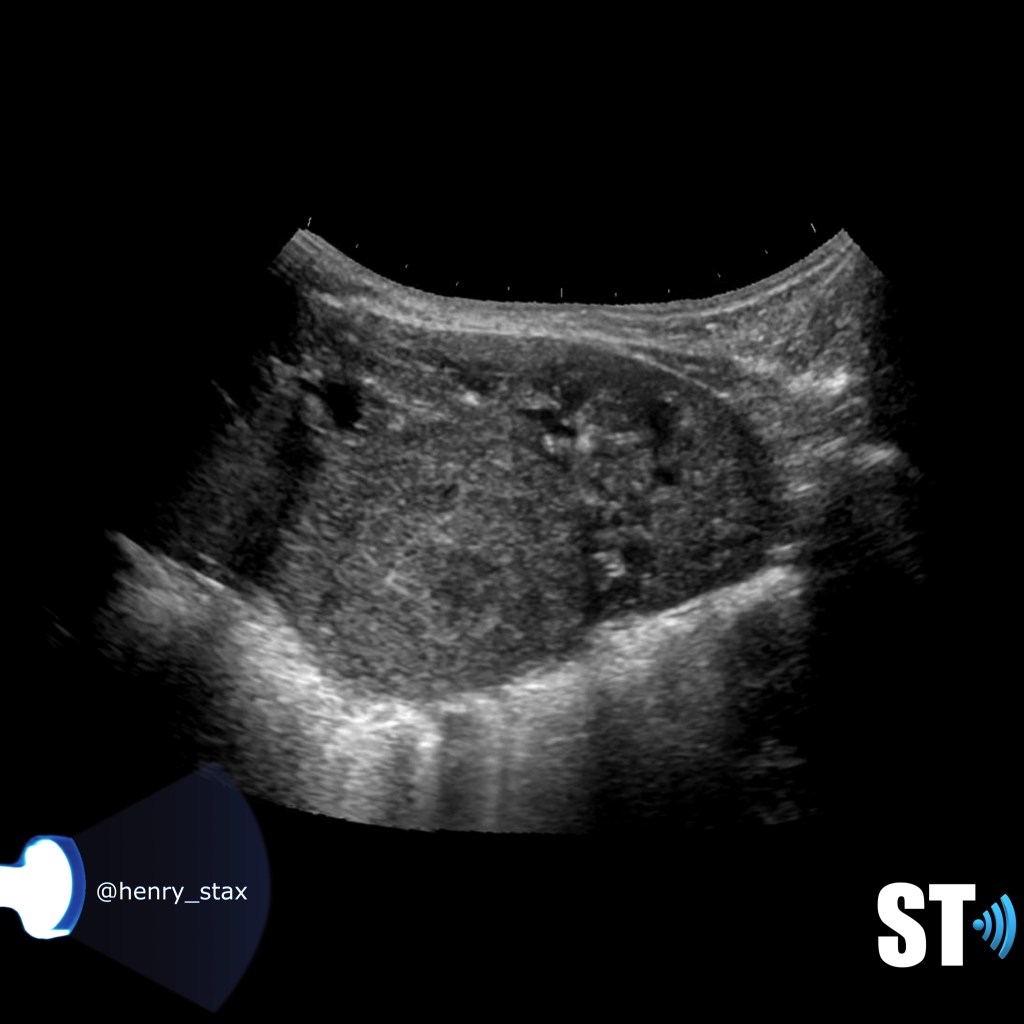

ADPKD

In Autosomal Dominant Polycystic Kidney Disease (ADPKD) the kidneys are normal at birth with cysts developing overtime. By age 30 years, approximately 68% of patients will have visible cysts by ultrasound. Eventually, virtually all patients develop cysts. The disease is transmitted in an autosomal dominant pattern, meaning you only one abnormal gene from one parent.

One abnormal gene from one parent

- Adult

- 4-10% of all cases of ESRF

- Kidneys appear normal early on

- Liver, pancreas and spleen cysts